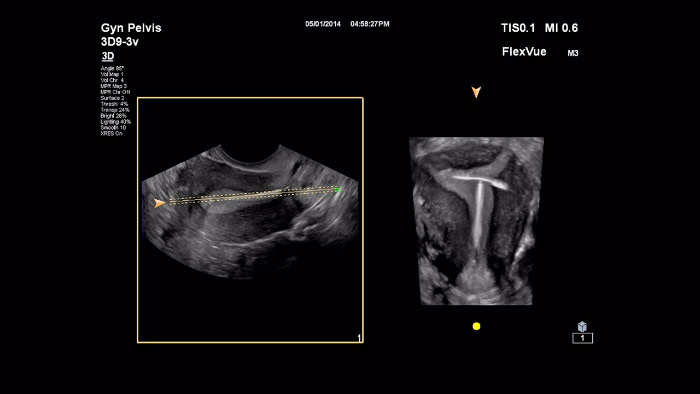

In deze video presenteert Dr. Michael Ruma de FlexVue, het geavanceerde 3D-beoordelingshulpmiddel van Philips. Met FlexVue kunnen in technisch opzicht moeilijke anatomische weergaven van 3D-volumes die essentieel zijn voor diagnose van pathologie op het gebied van verloskunde/gynaecologie eenvoudig worden gevisualiseerd.

We hebben verschillende workflowverbeteringen, zoals TouchVue, MPR Touch, FlexVue en aReveal, die de 3D-workflow intuïtiever en gebruiksvriendelijker maken, zodat het werken met deze waardevolle klinische tool gemakkelijker wordt. De combinatie van Philips TouchVue en MPR Touch biedt een eenvoudigere, meer intuïtieve methode voor 3D-workflow dan traditioneel wordt aangeboden. Met simpele vingerbewegingen op het aanraakscherm van het systeem kan de gebruiker de rotatie van 3D-volumes op alle assen eenvoudig regelen en de grootte en positie van MPR-parameters in alle weergaven bepalen. Gebruikers moeten de gewenste sectievlakken binnen grote 3D-volumes snel kunnen visualiseren. FlexVue is een uiterst veelzijdig hulpmiddel, waarmee in technisch opzicht moeilijke anatomische weergaven van 3D-volumes eenvoudig kunnen worden gevisualiseerd, die essentieel zijn voor diagnose van pathologie op het gebied van verloskunde/gynaecologie. FlexVue geeft structuren in hun geheel weer in een geprojecteerde planaire weergave. In tegenstelling tot traditionele 3D-bewerkingshulpmiddelen kunnen zelfs structuren met een ronding, zoals de foetale wervelkolom en baarmoeder in de gynaecologie, met FlexVue eenvoudig in hun geheel worden gevisualiseerd in een groot aantal orthogonale vlakken. aRevealA.I. is een geavanceerde functie van Philips AIUS die irrelevante 3D-informatie automatisch verwijdert en snel het gezicht van de foetus in 3D laat zien. Handmatige bewerking van de 3D-dataset van het gezicht van de foetus is niet langer nodig.

Philips biedt ultra-breedbandtechnologie die nog nooit eerder gezien is in echografie voor verloskunde/gynaecologie, zelfs niet op premiumniveau. De Philips eL18-4 ultra-breedbandtransducer biedt een fantastische gedetailleerde resolutie in 2D, samen met de penetratie die nodig is om vertrouwen in diagnoses te bieden, met name in de cruciale vroegtijdige verloskundige onderzoeken. Andere transducers, zoals de V9-2, C5-1, C9-2 3D9-3v, bieden ook een voortreffelijke beeldkwaliteit voor een grote verscheidenheid aan klinische aandoeningen en patiënthabitus om vertrouwen in diagnoses te bieden in de cruciale vroegtijdige verloskundige onderzoeken.